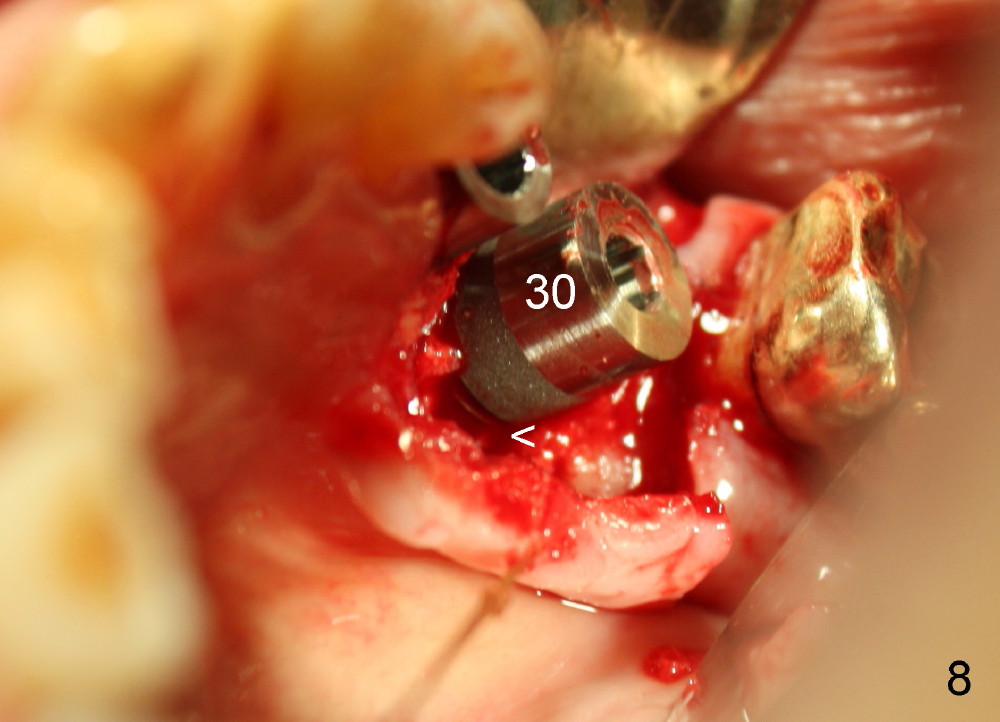

Three months later, the B-L width at the site of #29 is significantly reduced (Fig.4). Upon X-ray exam, there is decreased bone density between these two sockets (Fig.5 *). Socket preservation seems not to live its expectation. The obvious advantage is formation of callus-like bone in the molar socket (Fig.6 *, between the buccal (B) and lingual (L) plates). The significant decrease in the buccolingual width at the site of #29 is associated with buccal plate crack during implantation (Fig.7 *). At the site of #30, the lingual plate is so low that there is implant thread exposure (Fig.8 <). Mixture of autogenous bone (harvested from drilling with Bicon reamers) and synthetic bone (Osteogen) is placed mainly buccal to the implant #29 and lingual to #30 (Fig.9), followed by collagen membrane. Bone density between these two implant increases due to the bone grafting (Fig.10 *, as compared to Fig.5). In fact, the implant at the site of #29 is found loose 1 month postop.